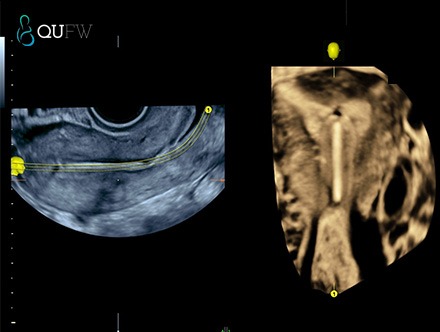

4D reconstructed image (VCI image) of correct placement of an IUCD within the endometrial cavity